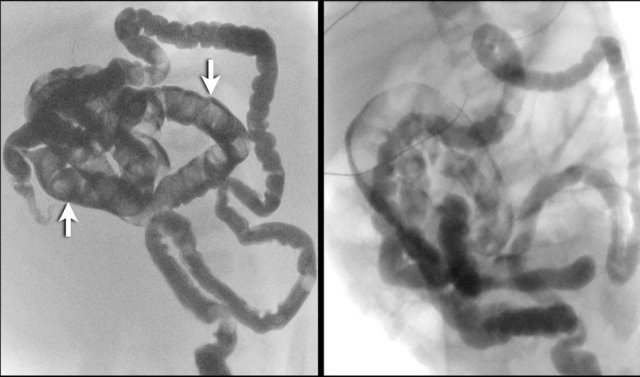

Here two cases of meconium ileus.

There is a microcolon and there are multiple meconium pellets in the distal small bowel (arrows).